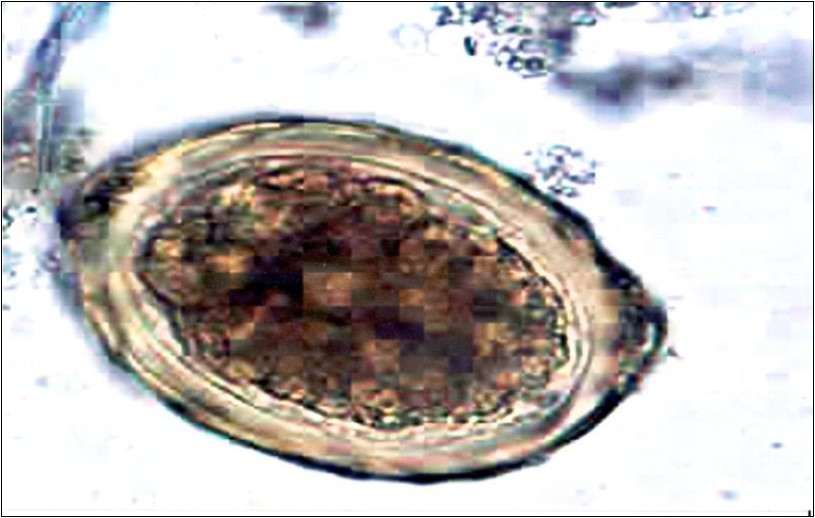

The present study was carried out to study the prevalence of intestinal parasitic on several school children in Damanhour and some of its villages. The result of the present study has been illustrated under the following items; socio-demographic and environmental characteristics of the studied sample, prevalence of intestinal parasitic infection among cases, in stool samples, distribution of the studied cases according to gender, distribution of the studied cases according to demographic data and comparison between the two studied groups according to the overall distribution on intestinal protozoa infection by sex. (Figure 1, Figure 2, Figure 3, Figure 4, Figure 5, Figure 6).

Figure 4.Schistosoma mansoni egg

Schistosoma mansoni egg